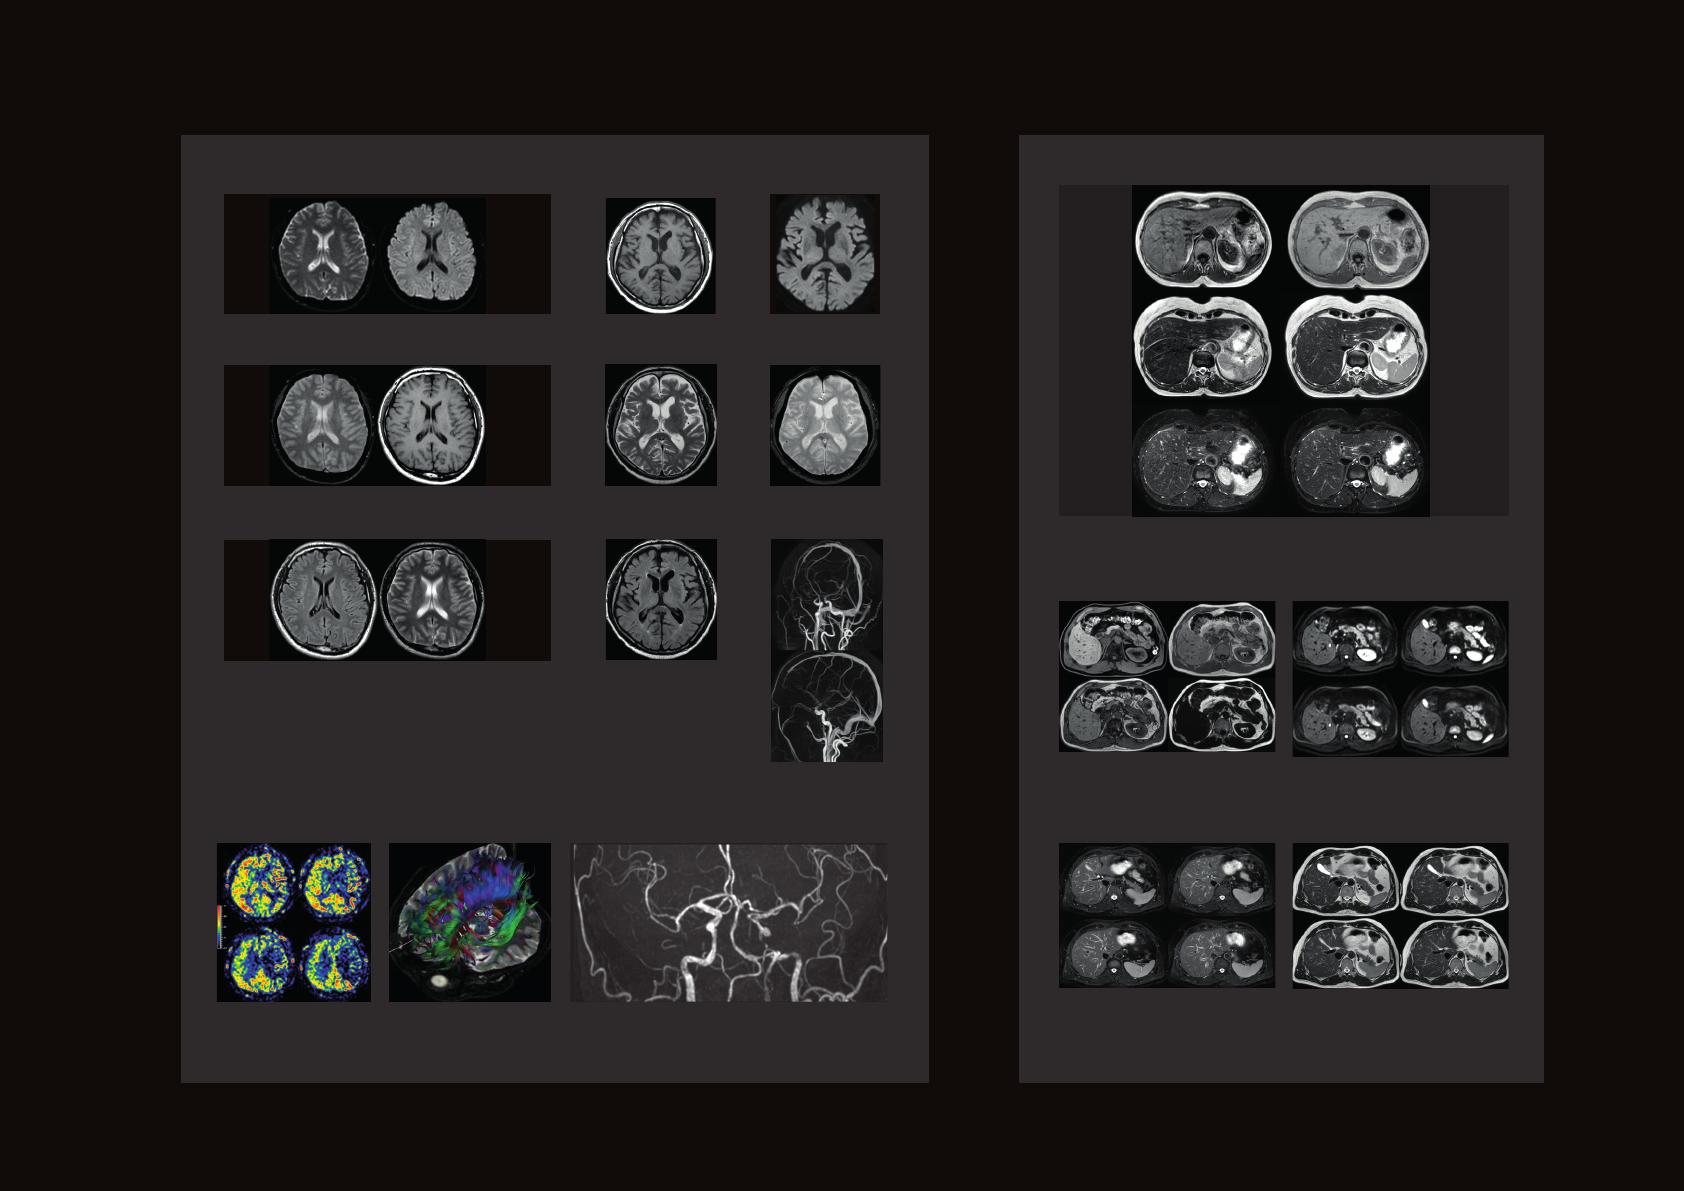

Access a wide range of applications

Prodiva 1.5T CS delivers access to a wide range

of advanced applications for brain, body, MSK,

oncology and cardiac examinations. Now you

can attract new referrals and generate additional

revenue.

Robust techniques for routine high-quality

imaging

Prodiva 1.5T CS gives you access to imaging

techniques such as fat suppression, motion

correction and metal artifact reduction to

overcome some of the most common issues that

result in inconclusive exams and re-scans.

Neuro Body

Body MVXD T2 MVSPIR

Brain Tra FFE

Brain Tra FLAIR

Brain Tra DWI pCASL tmp1

pCASL tmp3

pCASL tmp5

pCASL tmp4

MIP PCA

pCASL tmp2

Abd mDIXONall

Abd mvxdSPIR

Abd DWI

Abd mvxdpCASL DTI1a TOF Aneurysm